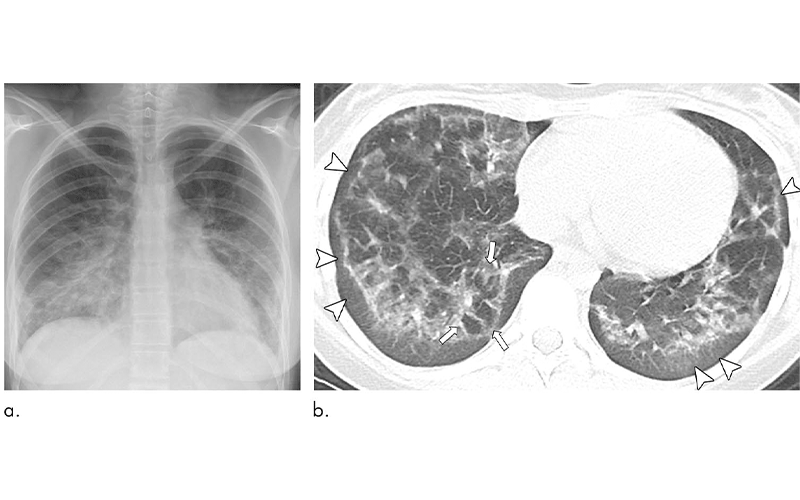

The results showed characteristic chest X-ray and CT findings. Bilateral and symmetric ground-glass opacity in the lungs, frequently associated with consolidation, often of lower lobe predominance, was the key imaging finding. On CT, subpleural sparing was also visualized in 79% of patients.

“Another imaging feature observed on CT in 36% of our pediatric patients with EVALI, was the reversed halo sign, which is characterized by the presence of a central ground-glass opacity surrounded by denser consolidation of crescentic shape or complete ring,” Dr. Artunduaga said.

Dr. Artunduaga noted that chest X-ray alone does not allow the sufficient characterization of the patterns of EVALI in pediatric patients and, therefore, CT is needed for a complete assessment.